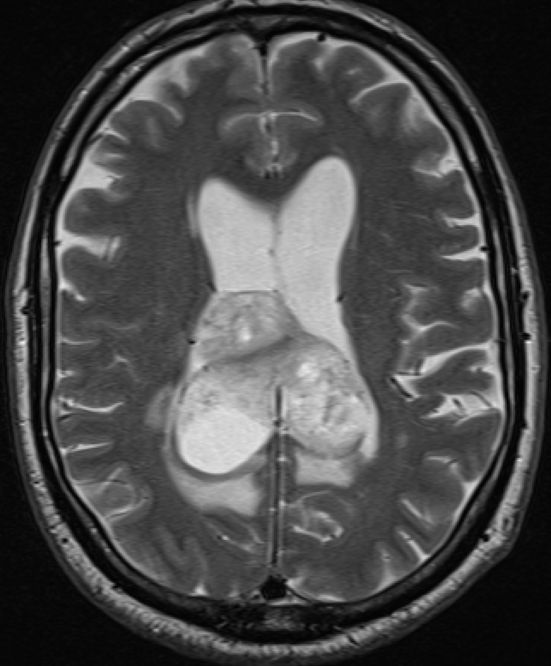

Schmetterlingsgliom des hinteren Balkens |

62-jähriger Mann mit torkeligem Gang, Amnesie und Verwirrtheit. Schmetterlingsgliom des hinteren Balkens.![]() |

![]() |

![]() | |